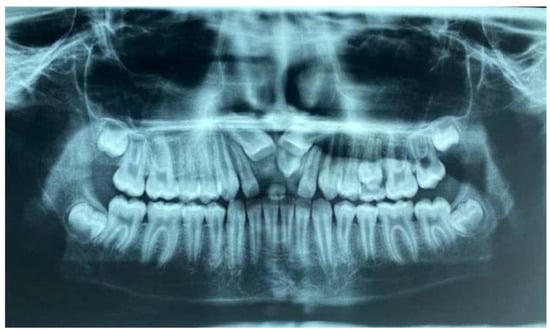

- Ortopanthomography X-ray (OPG X-ray) to evaluate the problem in relation to the entire arch, adjacent tooth and the staging of the eruption of the other dental elements.

2.2. Clinical Exams and Diagnosis

2.3. Therapeutic Plan

3. Results

| Values | Normal | |

|---|---|---|

| SNA | 80.4° | 82°+/−2° |

| SNB | 78.8° | 80°+/−2° |

| ANB | 1.6° | 2°+/−2° |

| GONIAC ANGLE | 116.1° | 130°+/−7° |

| INTERINCISIVE ANGLE | 98.4° | 131°+/−6° |

| SUPERIOR INCISOR ANGLE | 51.2° | 22°+/−2° |

| INFERIOR INCISOR ANGLE | 28.9° | 25°+/−2° |